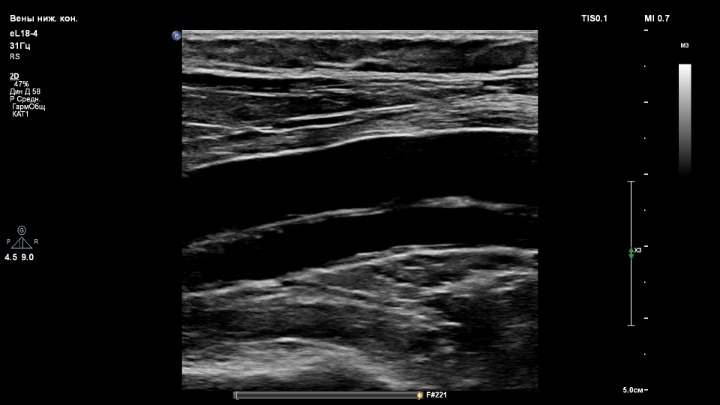

2. Датчик eL18-4

Сложно судить, ведь настройки В-режима в каждом скрине разные

- вены нижних конечностей для датчиков L12-3 и eL18-4;

- вены для датчика L18-5.

Глубина сканирования одинаковая, 5 см.

Выбирал предустановленные настройки путём нажатия пресета:Сложно судить, ведь настройки В-режима в каждом скрине разные

Если покупать один линейный датчик, то тогда это eL18-4.

Очень мне понравился. Он прекрасно работает и на низких частотах с достойной картинкой сосудов, и на высоких частотах (щитовидная, молочные железы, мягкие ткани). У аппарата 4 активных порта, 4 датчика - ничего не надо переставлять. Это очень удобно. И тут датчик eL18-4 выполняет свою работу на 100%.

Когда работаю на аппарате с одной линейкой eL18-4, то доволен и картинкой вен нижних конечностей.

Но при работе на аппарате с 3-мя линейками, сравнивая их, я всё же для вен беру датчик L12-3.